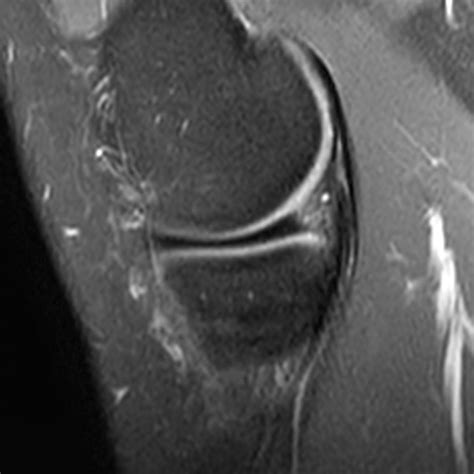

• Magnetic Resonance Imaging (MRI) to provide detailed images of the meniscus and surrounding structures. MRI is particularly useful in identifying the location and extent of the tear.